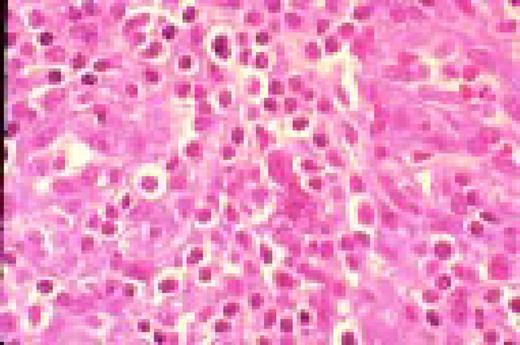

Slide L49

HIV-associated lymphadenopathy, lymph node, H&E. Multinucleated cells are clearly appreciated, as is a venule.FIG49